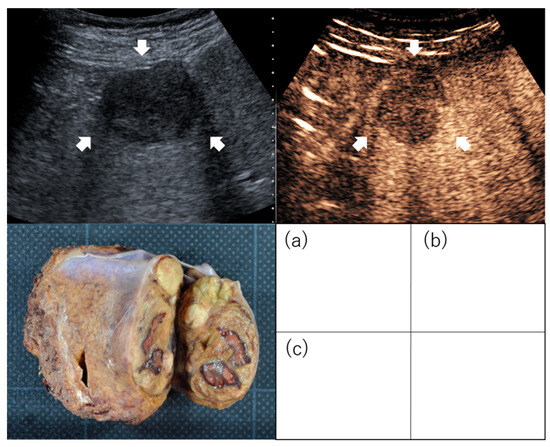

2.1. Gross Classification

- -

- The small nodular type with indistinct margin.

- The simple nodular (SN) type, with a clear round shape.

- The simple nodular with extranodular growth (SNEG) type, with a clear round shape and one or more tumor growths coexisting around the nodules.

- The confluent multinodular (CMN) type, consists of clusters of small nodules.

- The infiltrative type.

- Hui, A.-M.; Takayama, T.; Sano, K.; Kubota, K.; Akahane, M.; Ohtomo, K.; Makuuchi, M. Predictive value of gross classification of hepatocellular carcinoma on recurrence and survival after hepatectomy. J. Hepatol. 2000, 33, 975–979. [Google Scholar] [CrossRef]

- Shimada, M.; Rikimaru, T.; Hamatsu, T.; Yamashita, Y.-i.; Terashi, T.; Taguchi, K.-i.; Tanaka, S.; Shirabe, K.; Sugimachi, K. The role of macroscopic classification in nodular-type hepatocellular carcinoma. Am. J. Surg. 2001, 182, 177–182. [Google Scholar] [CrossRef]

- Sumie, S.; Kuromatsu, R.; Okuda, K.; Ando, E.; Takata, A.; Fukushima, N.; Watanabe, Y.; Kojiro, M.; Sata, M. Microvascular Invasion in Patients with Hepatocellular Carcinoma and Its Predictable Clinicopathological Factors. Ann. Surg. Oncol. 2008, 15, 1375–1382. [Google Scholar] [CrossRef]

- Hatanaka, K.; Chung, H.; Kudo, M.; Haji, S.; Minami, Y.; Maekawa, K.; Hayaishi, S.; Nagai, T.; Takita, M.; Kudo, K.; et al. Usefulness of the post-vascular phase of contrast-enhanced ultrasonography with sonazoid in the evaluation of gross types of hepatocellular carcinoma. Oncology 2010, 78 (Suppl. S1), 53–59. [Google Scholar] [CrossRef]

| Hatanaka et al. [28] | 29 | Solitary and ≤5 cm ≤3 tumors and ≤3 cm | LR | Gross type (SN type or non-SN type) | Sensitivity, 96%; specificity, 80%; accuracy, 90% |

| Li et al. [29] | 31 | Early stage | LR | Microvascular invasion | Non-SN type in the post-vascular phase image was an independent predictor of microvascular invasion (OR, 30.51; 95% CI, 2.335–398.731, p = 0.009). Sensitivity, 93.3%; specificity, 81.3%; positive predictive value, 82.4%; negative predictive value, 92.9% |

| Nuta et al. [30] | 73 | Solitary and ≤5 cm | LR | Gross type (SN type or non-SN type) Outcome (recurrence) | In the post-vascular phase, predictability for high-grade malignant potential was as follows: sensitivity was 93%, specificity was 85%, positive predictive value was 97%, negative predictive value was 73%, and accuracy was 92%. Irregular defect pattern was one of the independent factors for metastatic recurrence (HR, 4.388; 95% CI, 1.008–19.089; p = 0.049). |